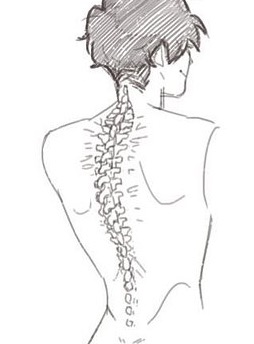

- 脊柱功能性疼痛是怎么回事?治疗方案是什么? 布骨康复医疗中心 ,2020-02-03

- 脊柱的最长部分,脊背主要负责保护脊髓。虽然它是由肋骨支撑的,但它仍然可能是疼痛和不适的部位。在电脑前工作常常是问题的原因! 背或胸椎有12节椎骨,从最后一节颈椎到第一节腰椎,呈自然弯曲,称为后凸。它的作用是支撑身体和保护脊髓。肋骨与背脊骨相连。 .....

- 脊柱是我们身体的中心支柱,如果出现背痛,解决方案是什么? 布骨康复医疗中心 ,2020-02-02

- 脊柱,也被称为脊柱或脊椎骨,是我们身体的中心支柱。 它的主要作用之一是引导躯干允许我们做的许多动作:弯曲、伸展、旋转、倾斜。它由24个椎骨组成:7个颈椎骨,12个胸椎骨和5个腰椎椎骨,5个骶骨椎骨和3 - 5个尾骨椎骨。像所有的关节一样,椎骨是由许多韧带和肌肉连接在一起的。它们由一个椎间盘隔开,椎.....